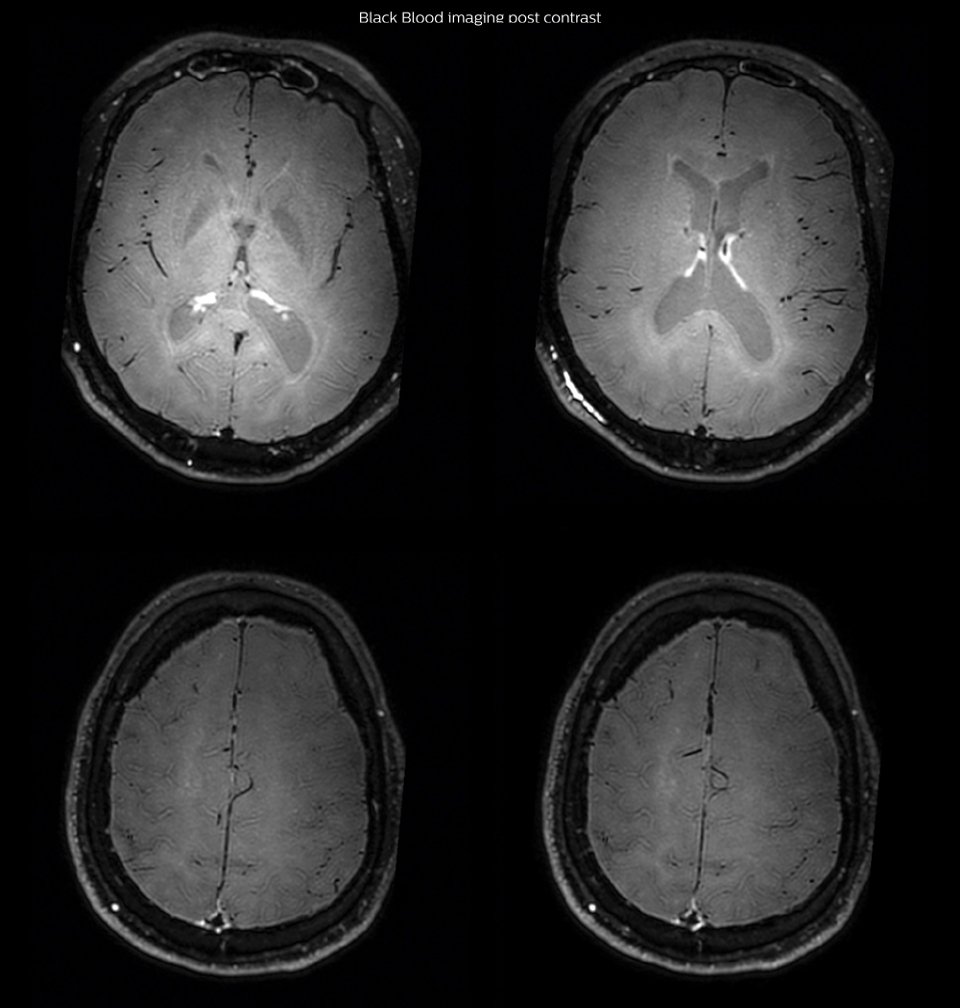

After a conventional routine MR imaging examination, the suspicion of vasculitis arose, therefore we performed an MRI including Black Blood imaging in a separate session. The dedicated ExamCard includes diffusion, FLAIR, MR angiography using TOF, and 3D T1 MRA with bolus injection. This ExamCard also includes Black Blood imaging before and after contrast. This examination was performed on our Ingenia 3.0T. Black Blood scan time 4:39 min, acquired voxel size 0.75 x 0.75 x 1.0 mm, 21 slices.

Arrows show vessel wall enhancement which appears concentric and homogeneous in different cerebral territories.

On the routine MR sequences that we did, we could see acute ischemic lesions. We see them very well on the diffusion images, where acute ischemic lesions usually appear with high signal intensity and restricted diffusion. However, the etiology of these lesions cannot be derived from these images. An area of restricted diffusion was seen in the anterior cerebral artery territory and we concluded it was an ischemic lesion. On MR angiography we can just see if there is stenosis or vessel occlusion, but it does not provide us information on the etiology of this kind of lesion. So, we decided to perform Black Blood imaging. The presence and the pattern of vessel wall enhancement on Black Blood imaging, can help us to determine the etiology of the lesion. differentiate vasculitis from other causes of vasculopathy, such as atherosclerosis, with a high specificity [1-3]. In an atherosclerotic lesion, vessel wall thickening and enhancement are usually eccentric, while in vasculitis the wall thickening and enhancement are usually concentric, homogenous, and in a long portion of the vessel. of patients whenever their treatment is installed in order to determine the efficacy of a particular treatment. In this case the Black Blood imaging helped us to suggest the diagnosis of HIV-related brain vasculitis.

Impact of Black Blood imaging for this patient

had, such as glucose intolerance, arterial hypertension and hypocholesteremia, his lesions could be atherosclerotic lesions or vasculitis, conditions which require different treatment. Especially in this patient with HIV infection causing the vasculitis, treatment of the two conditions is different. The results of MRI with Black Blood imaging, helped to choose the preferred treatment for this patient, which was based on antiviral medication rather than an antiaggregant or anticoagulation treatment which is usually given to patients with risk of ischemia based on atherosclerotic lesions. One month after beginning the antiviral treatment, the same MRI examination was repeated and again 8 months after the beginning of treatment. On follow-up images, we see the enhancements have almost disappeared. So in case of this patient, the MRI exam with Black Blood imaging helped us to give the patient the appropriate treatment and also allowed us to noninvasively confirm the treatment response.

Black Blood imaging after one month

After one month of treatment, post-contrast Black Blood images at the exact same levels as in the figure above show disappearance of the vessel wall enhancements which were seen on the previous examination.